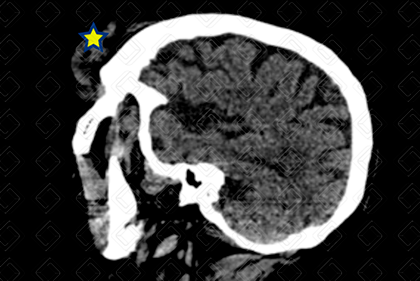

Texto alternativo para a imagem Figura 2. Créditos: Dra. Elazir Mota - Rio de Janeiro/RJ

Descrição da lesão: Tomografia computadorizada de crânio. A umento das partes moles extracranianas na região frontal e periorbitária esquerdas (asteriscos), caracterizando hematoma subgaleal. Não há extensão intracraniana ou sinais de fratura.

Hematoma subgaleal: A umento extracraniano das partes moles, sem extensão intracraniana. Em geral, ocorre por ruptura de veias emissárias que drenam o couro cabeludo, com acúmulo de sangue entre periósteo superficial e aponeurose do músculo do couro cabeludo.